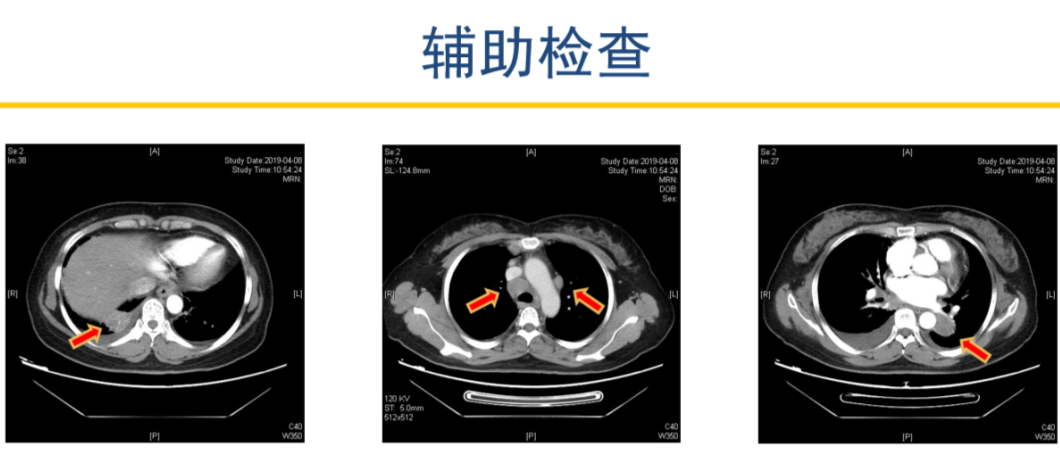

患者2019-04-08 胸部增强CT,显示左肺下叶占位并纵隔、双肺门、右锁骨上多发肿大淋巴结,考虑肺癌可能。右下肺占位,建议抗炎治疗后复查。

2019-04-12 PET-CT显示①右肺下叶后基底段胸膜下软组织密度肿块(大小26*30mm)。

②左肺下叶纵隔旁软组织密度肿块(大小28*31mm)。

③双肺门、纵隔内隆突下、气管旁、主肺动脉窗、血管前间隙、右侧颈部Ⅴ区及锁骨区多发增大淋巴结。

至此为止,患者的诊断为:肺恶性肿瘤 小细胞癌 广泛期 cT4N3M0 IIIC期(病灶1:右肺下叶,病灶2:左肺下叶),此时先给予标准化疗方案,EP方案:依托泊苷100mg/㎡ d1-3+顺铂75mg/㎡ d1-2 q21d*2。结果如下:

可以看到右肺下叶的病灶有明显缩退,但左肺下叶情况未能改善,因此我们再次在CT引导下左肺占位穿刺活检术。在给予第3周期EP方案化疗方案的同时,进行病理检测,发现理:左下肺病灶为低分化癌,符合腺癌,不除外复合性癌可能。通过肺癌常见基因检测(ARMS法)确定为ALK融合阳性。